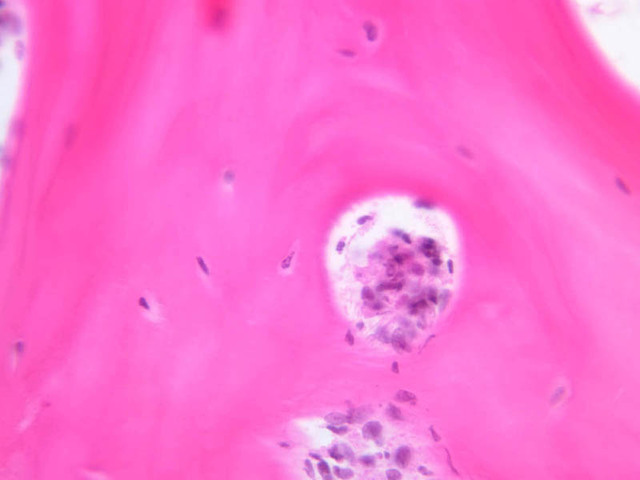

Compact bone, (slide A-1, human ground bone [2.5x, 10x, 20x-labeled, 40x] [2.5x, 10x-labeled, 20x, 20x]) shows a cross section of ground bone. The slide mount is very thick and you may not be able to focus using your 40x objective. It is prepared by grinding down a thin piece of bone until it can be viewed under the microscope. The Haversian system can be clearly seen in this type of preparation. The lamellae are indicated by the concentric layers of dark lentiform lacunae. Canaliculi are thin threads running from the lacuna of one lamella to the lacunae of adjacent lamellae. The complex of osteocytes embedded in concentric rings (lamellae) of bone around Haversian canals forms an osteon, a structural unit of compact bone. Between osteons occur clusters of osteocytes not concentrically oriented around a canal. These clusters form interstitial lamellae, remnants of earlier osteons. At the outer and inner edges of a bony shaft, lamellae usually parallel the periosteum and endosteum, forming circumferential lamellae. In living bone, blood vessels which penetrate the bony shaft from the vascular periosteum or connect parallel Haversian canals cross the bone at an angle and are not surrounded by bony rings. These oblique canals are visible in dried bone and are known as Volkmann's canals. Note that in this section of dried bone the soft tissues, for example, cells, blood vessels, and periosteal tissue, are not represented. Only the insoluble matrix of the bone resists drying and thus can be ground into thin sections.

Cement lines are refractile lines separating the individual osteons. Can you identify the interstitial systems which are partial osteons? These are seen as irregular Haversian systems between the complete Haversian systems. Can you identify any Volkman's canals?

Decalcified bone is present in slide slide A-3 (intervertebral disk, H&E [2.5x, 10x-labeled, 20x, 40x] [2.5x, 10x, 20x, 40x] [2.5x, 10x, 20x-labeled, 40x, 40x]). This process enables us to visualize the cellular elements of bone. Each bone cell or osteocyte, as in cartilage, lies in a lacuna, but bony lacunae are irregularly shaped due to the radiating canaliculi through which cell processes of osteocytes make contact with each other. An impression of the density of bone matrix and the irregular shape of encased osteocytes due to their surface processes can be gained by an electron micrograph of mineralized bone. Because of the matrix density, nutrient substances pass from the Haversian canals to each osteocyte through a series of lacunae and canaliculi. The endosteum is represented by a single layer of thin flat nuclei on the surface of the marrow cavity. Identify the osteocytes and their cell processes in the canaliculi. Look for the outer circumferential lamellae adjacent to the periosteum. Can you see any inner circumferential lamellae adjacent to the endosteum?